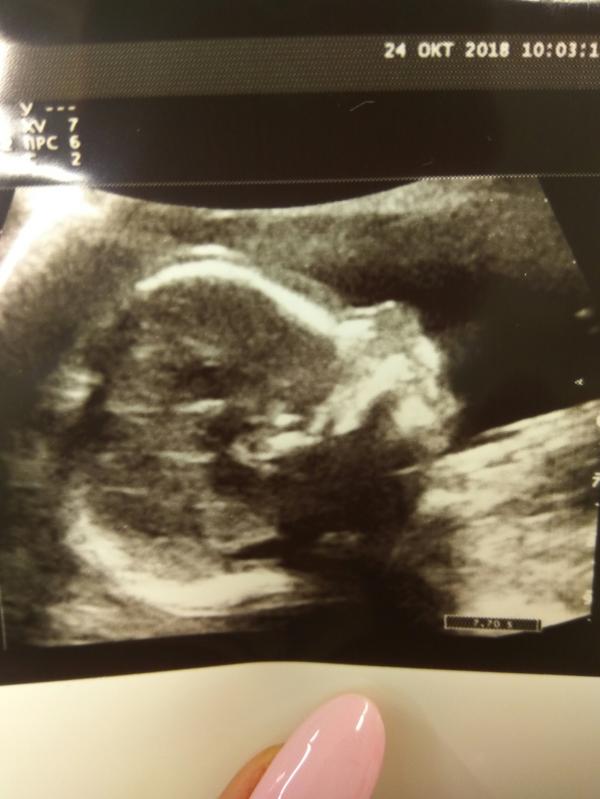

@kovner.ket мне не так повезло с узистом что делал фото , не такое хорошенькое как ваше)

Красотаааа